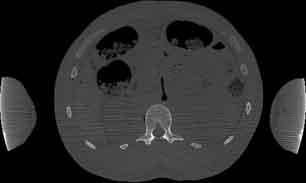

Visible Human male: Sectio transversalis 1600

CT

NMR

Pd                          / T2 \                         T1